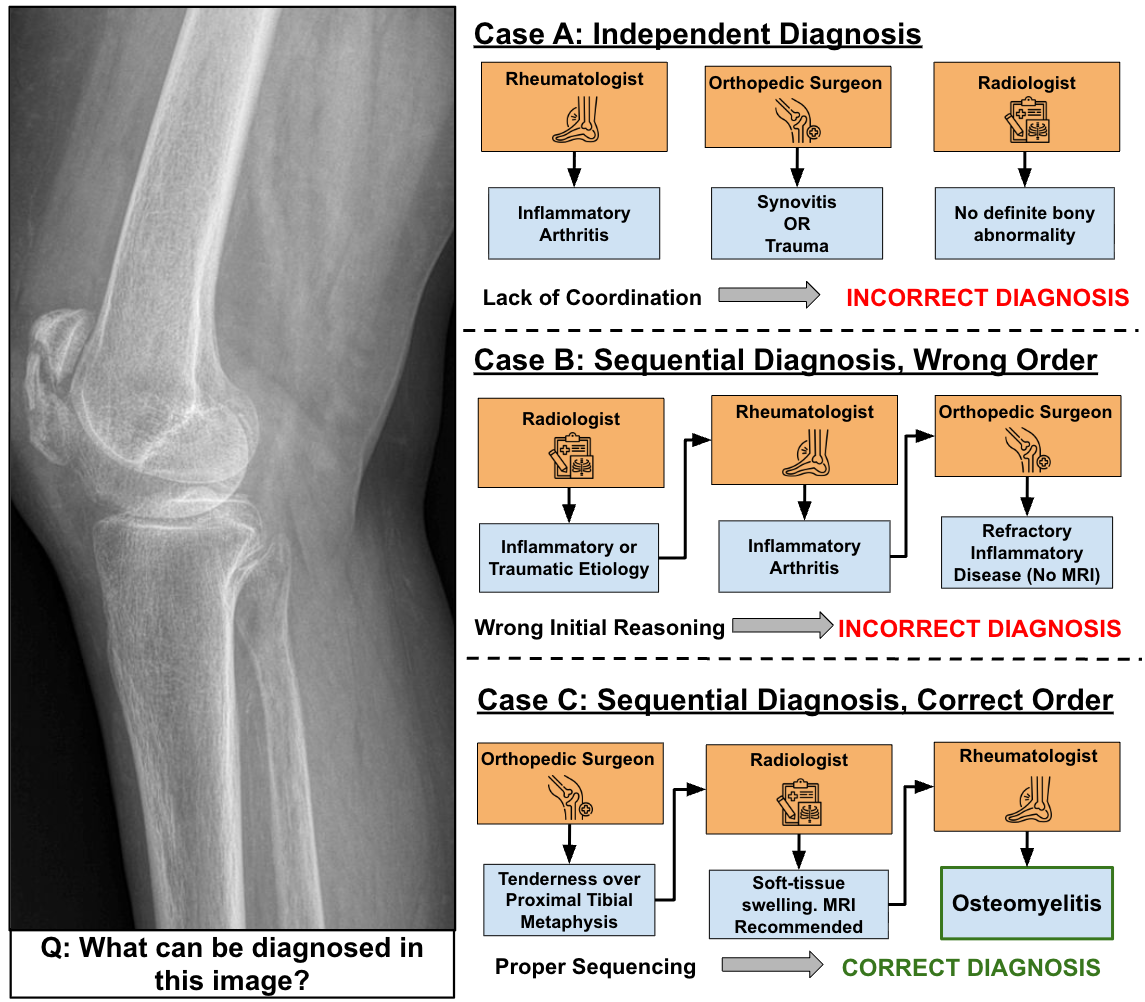

MedRoute: RL-Based Dynamic Specialist Routing in Multi-Agent Medical Diagnosis

Ashmal Vayani, Parth Parag Kulkarni, Joseph Fioresi, Song Wang, Mubarak Shah

arXiv preprint, 2026.